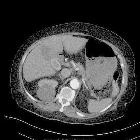

medical management of emphysematous gastritis with concomitant portal venous air: a case report. CT of the abdomen showing air in the stomach wall and portal venous system. Black arrow: Portal venous air. White arrows: Air in the stomach wall.